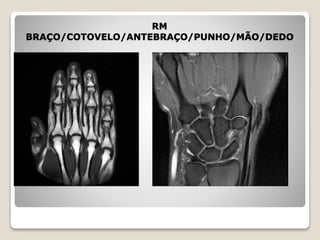

MEMBROS SUPERIORES-MMSS

 RM ombro

 RM braço

 RM cotovelo

 RM antebraço

 RM punho

 RM mão

 RM dedo

RM

BRAÇO/COTOVELO/ANTEBRAÇO/PUNHO/MÃO/DEDO